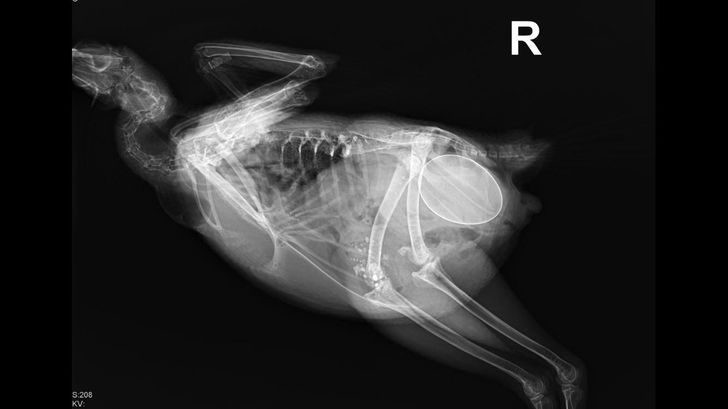

«Работа в ветеринарной клинике приносит свои радости. Такой, например, оказалась курица на рентгене»